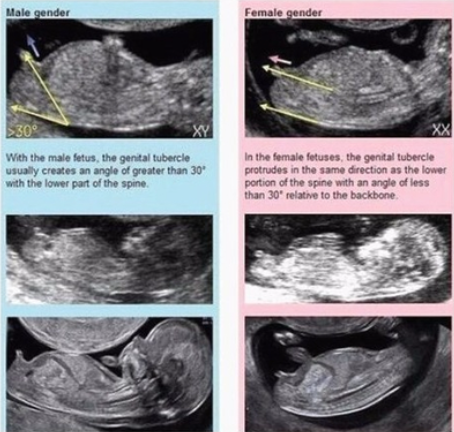

💡 초음파 각도법은 태아의 생식기가 발달하기 전, 초기 초음파로 성별을 예측하는 방법이에요.

✔ 임신 11~13주 사이 초음파에서 확인 가능!

✔ 태아 생식기의 각도가 30도 이상 위로 향하면 남아, 수평이면 여아일 확률이 높음